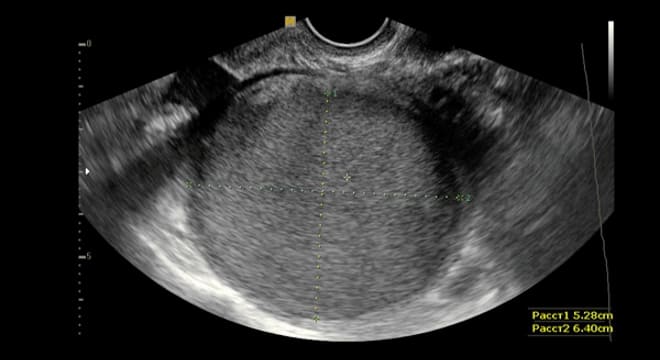

Параовариальная

Является анэхогенным образованием с тонкой капсулой, расположенным в области широких маточных связок.

Параовариальная киста может вызывать изменения в размерах матки и придатков, что хорошо видно при ультразвуковом исследовании. Размеры кисты варьируются от 5 до 20 см.

Стенка этого новообразования состоит из соединительной ткани с добавлением эластичных волокон, а внутренняя поверхность выстлана тонким эпителием.

В 60% случаев на УЗИ параовариальная киста правого яичника выявляется при её увеличении до 15 см. Образование на левом яичнике встречается несколько реже. Женщины, столкнувшиеся с данной патологией, часто испытывают сильные боли в нижней части живота, что заставляет их обратиться за медицинской помощью.